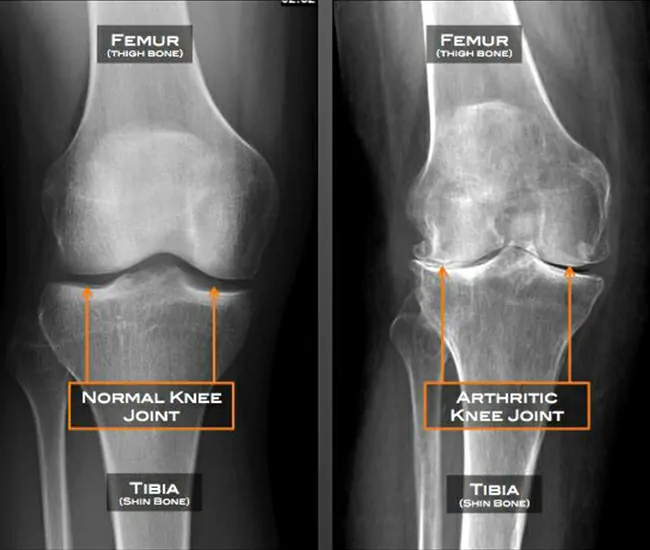

Knee osteoarthritis (OA) is a degenerative joint disease caused by the gradual breakdown of cartilage, ligaments, and bones in the knee joint. It leads to pain, stiffness, swelling, and reduced mobility.

1. Cartilage Degeneration – Loss of cushioning in the knee joint.

4. Osteophyte Formation (Bone Spurs) – Leads to stiffness & pain.